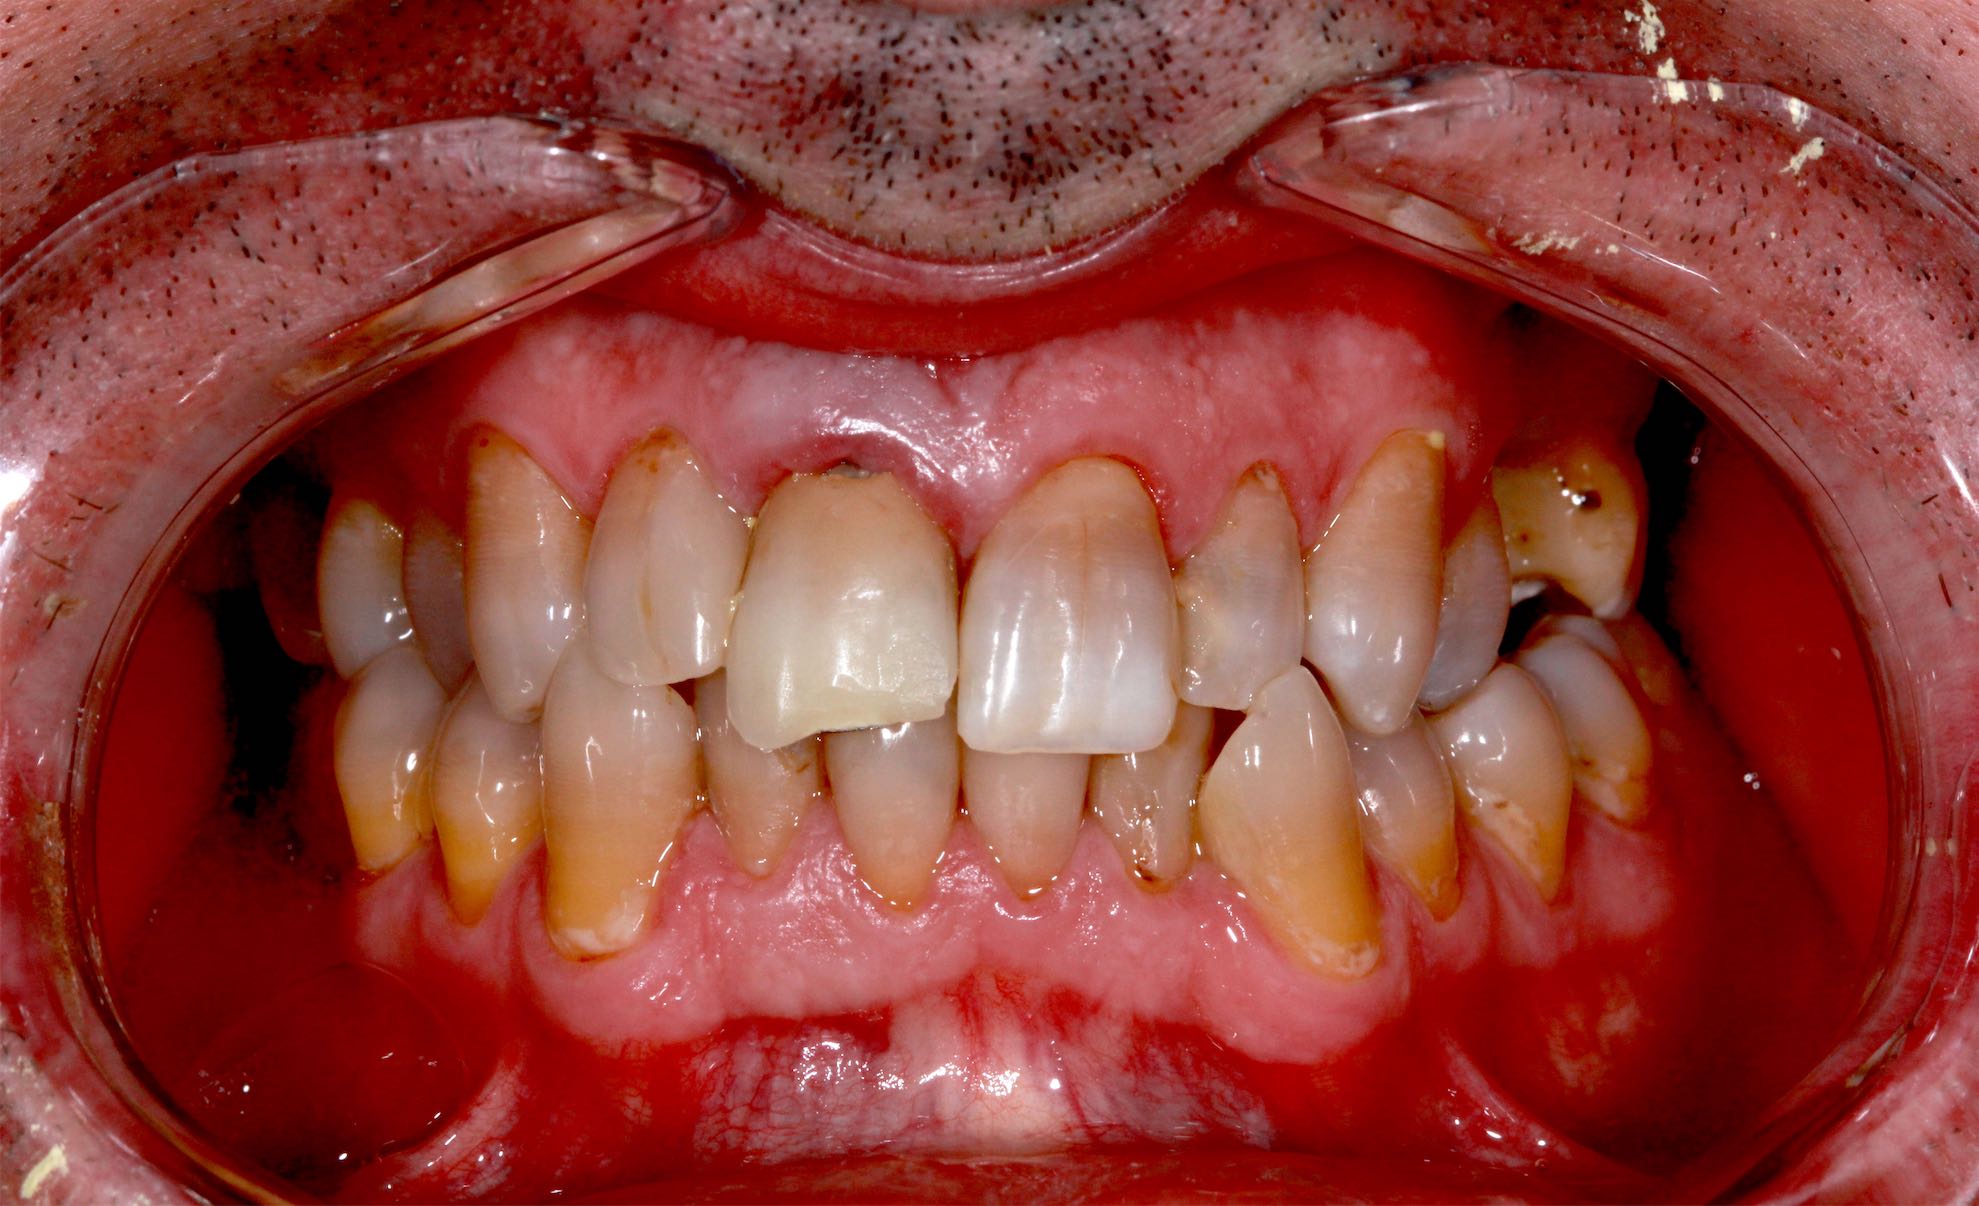

Periodoncia . Injertos de Encía

BeforeAfter